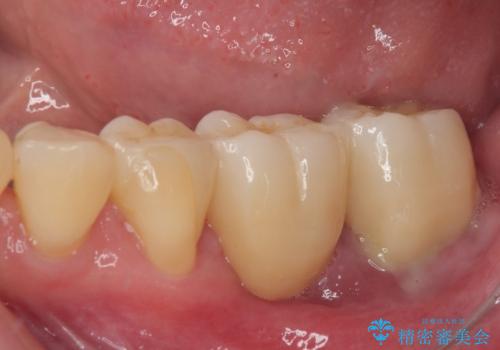

ブリッジから膿が出る 奥歯のインプラント治療

上顎は最後臼歯が欠損しているため、ブリッジの土台は抜歯し、元々の欠損部にインプラントによる補綴治療を行うこととしました。

支台歯の骨欠損は予想以上に大きく、即時荷重インプラント部への影響が心配されましたが、無事に最短期間で治療を終えることができました。